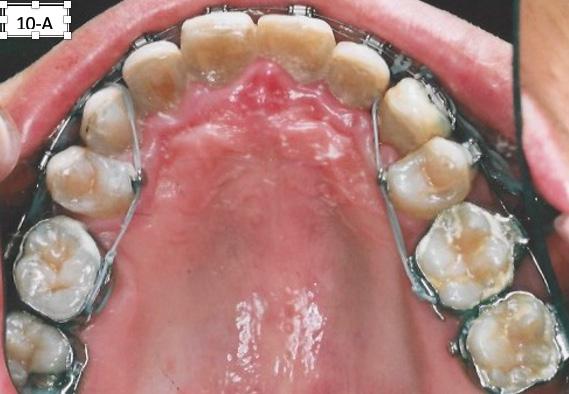

The side effect of protraction of the first molars is a mesiolingual moment (rotation). To neutralize this, the force must be applied, from the palatal aspect with the Power thread or the Elastomeric chain. The Power thread is attached to the lingual cleat of the molar bands, and it is stretched to the maximum, then tied to the arch wire between the cuspids and lateral incisors. A 3/16” – 4.5 oz Class III elastic was placed on the right side and a ¼”4.5 oz triangular elastic was placed on the left side to ameliorate the interdigitation (Figure 10-A, B, C).

FIG. oral mucosa FIG. 9C: Tissue guard, right lateral view FIG. 9D: Protraction of the first molar, left lateral view FIG. 10A: Lingual intra – Power thread, occlusal view FIG. 10B: Class II elastic, right lateral view FIG. 10C: Triangular elastic, left lateral view FIG. FIG. FIG. 12A: “W” with tail, right lateral view FIG. 12B: “W” with tail, left lateral view